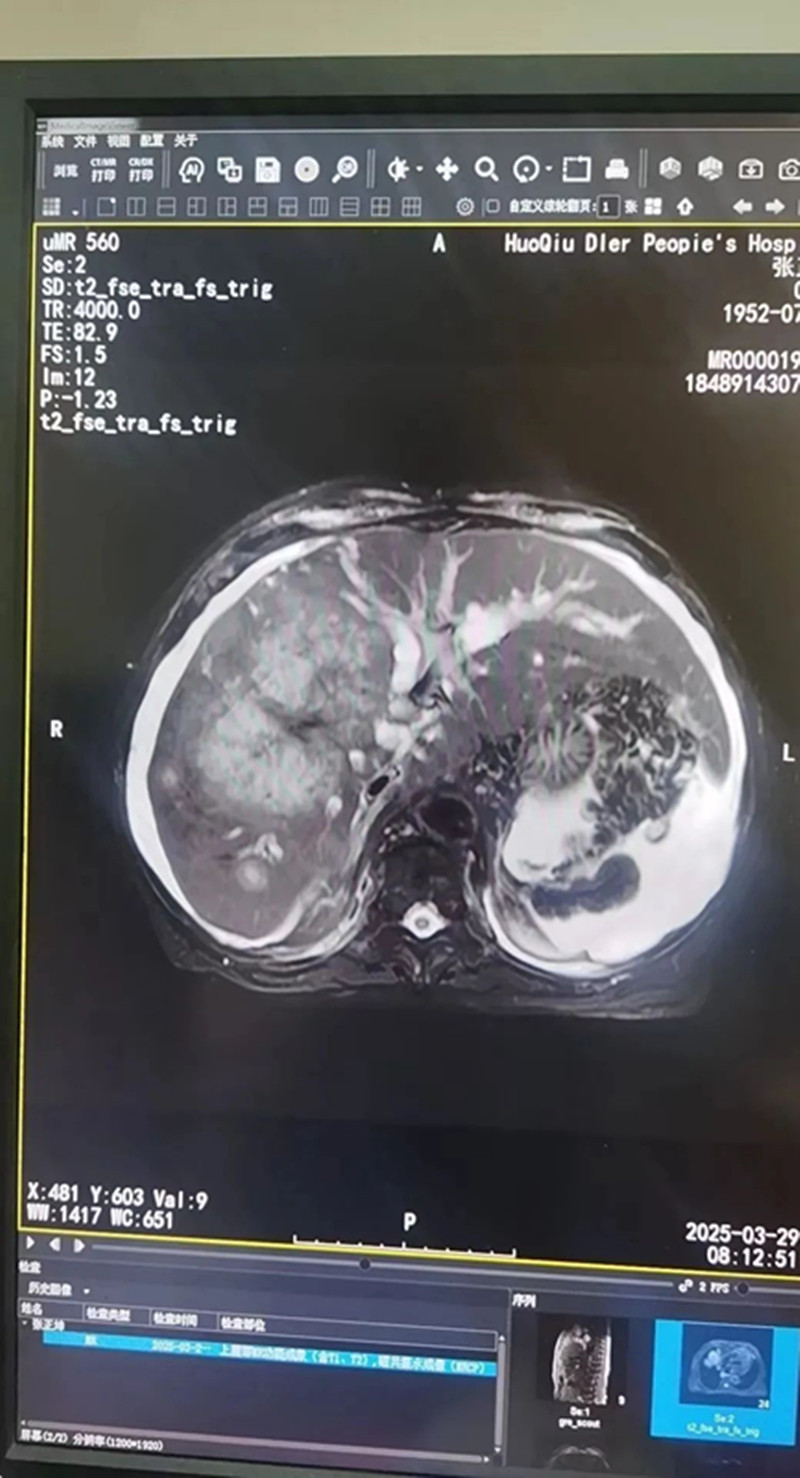

据了解,患者张某,男,72岁,确诊晚期胆管癌2月余,近1周患者出现腹痛、腹胀不适,伴有全身黄染,症状呈持续性无缓解,为求进一步诊疗收住县二院肿瘤内科。该科副主任医师陶黎明带领团队,经科内充分讨论评估和患者充分沟通后,遂对患者成功实施了PTCD术。术后患者症状得到明显改善。这场“穿刺攻坚战”的核心——经皮肝穿胆道引流术(PTCD)正是通过皮肤穿刺将引流管置入肝内胆管,将淤积的胆汁引出体外,缓解了黄疸危机,迈过了最险峻的一关。